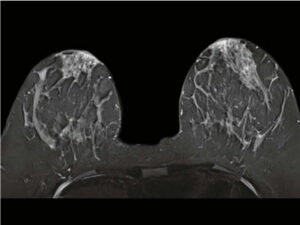

What to expect during your breast MRI

You’ll lie on your stomach with both breasts hanging freely into a cushioned recess containing a breast coil receiver. The bed moves into

the opening of the scanner, and you’ll be asked to lie still for up to 15 minutes at a time while images are acquired. Total exam time is usually an hour or less.